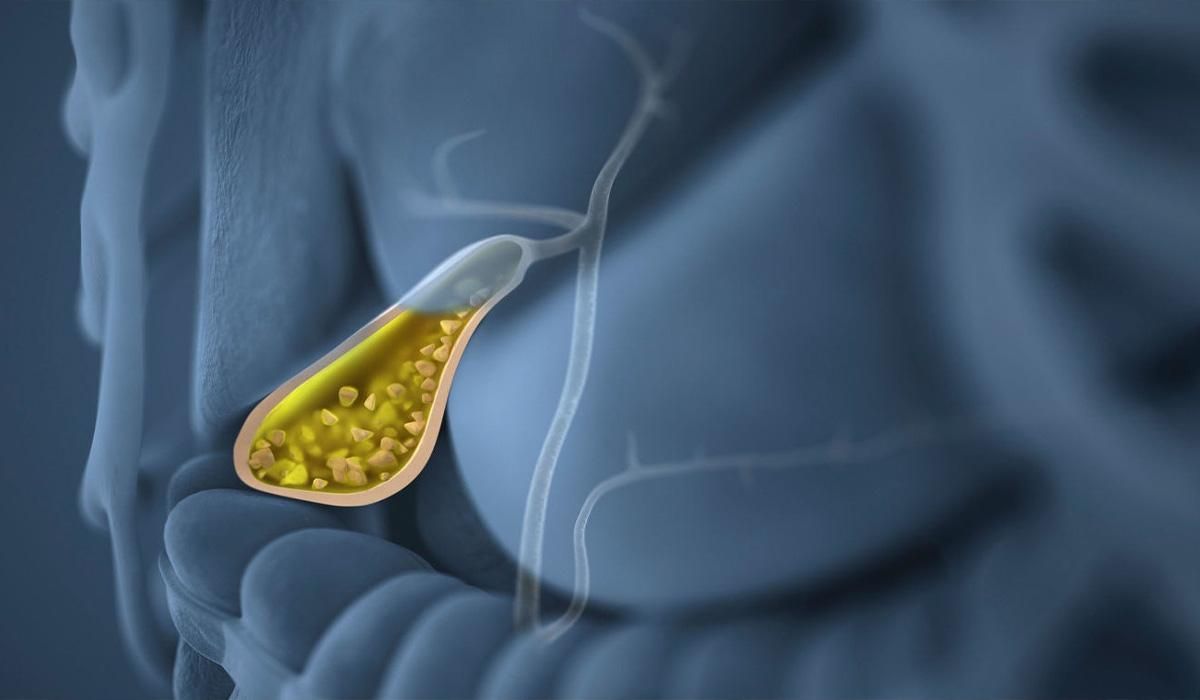

Попередні дослідження свідчать, що в процесах зародження утворюються кристали, зокрема, у випадку жовчного міхура – це кристали холестерину.

Вивчаючи структуру каменів, вчені виявили, що вони покриті слідами особливого типу лейкоцитів, що мають назву нейтрофільні гранулоцити. Ці клітини – перша лінія захисту організму від патогенних агентів, при виявленні кристалів вони також ідентифікують їх як загрозу.

"Атакуючи кристали, клітини помирають і покривають кристали своїм генетичним матеріалом, імітуючи сітку. Потім ця сітка обвивається навколо кристалів і об’єднує їх разом. Саме так і формуються камені, приймаючи різну форму".

Вивчаючи зразки жовчі, вчені виявили, що потрапляючи в липке середовище, сітки поєднуються разом з кристалами холестерину та кальцію.